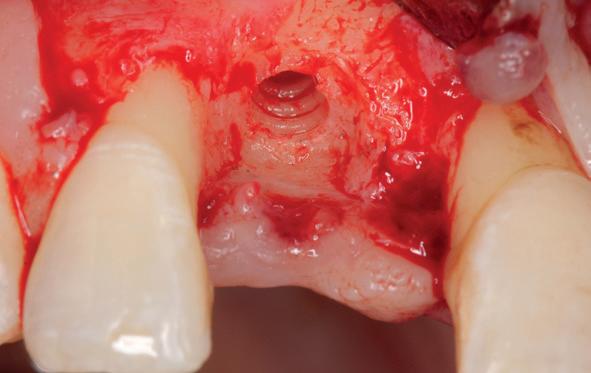

Implantologische behandelingen in het esthetische front vragen meer dan technische vaardigheid alleen. Ze vragen om overzicht, timing, vertrouwen en een team dat als vanzelf samenwerkt onder druk. Juist bij complexe casussen, waarin angst, infectie en hoge esthetische verwachtingen samenkomen, wordt zichtbaar hoe bepalend de rol van de tandartsassistent is.

Deze casus beschrijft een uitgebreide immediate implantaatbehandeling bij een patiënt die door meerdere collega’s werd geweigerd. Niet omdat de mogelijkheden ontbraken, maar omdat de complexiteit vroeg om een perfect afgestemde samenwerking. Het verhaal laat zien hoe de assistent in zo’n traject veel meer is dan een uitvoerende kracht of “mal”, maar een dynamische surgical guide die het proces mede stuurt, bewaakt en mogelijk maakt.De patiënt: wanneer alles samenkomt

Na het klinische onderzoek volgde het röntgenologisch traject. De CBCT liet precies zien wat we al vreesden: een front waarin het bot onregelmatig was, duidelijke radiolucenties rond de pijlers en een infectiegebied dat zich onder vrijwel de gehele brug had verspreid. Tegelijkertijd was er ook potentie. Net voldoende botstructuur om immediate implantaatplaatsing te overwegen, mits alles perfect gepland zou worden.